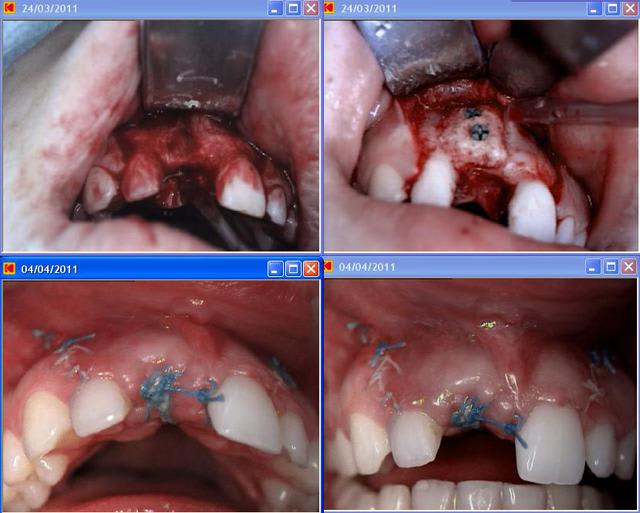

un cas tout chaud avec du puros. ( puros + membrane péricardum + PRF )

C'est mon unique cas donc pas de retour d'expérience.

A la journée, zimmer de l'année derniere , L'italien de 3dblock dont je ne rapelle jamais le nom avait montré pas mal de cas d'augmentation verticale comme celui-ci : http://www.3dblock.com/argoblog.asp?IDa=5 , avec une quasi absence de résorption. De même, Jabbour avait l'air de dire que bioblank se résorbais plus. Mais cela ne semble pas etre l'avis des utilisateurs eugénoliens...